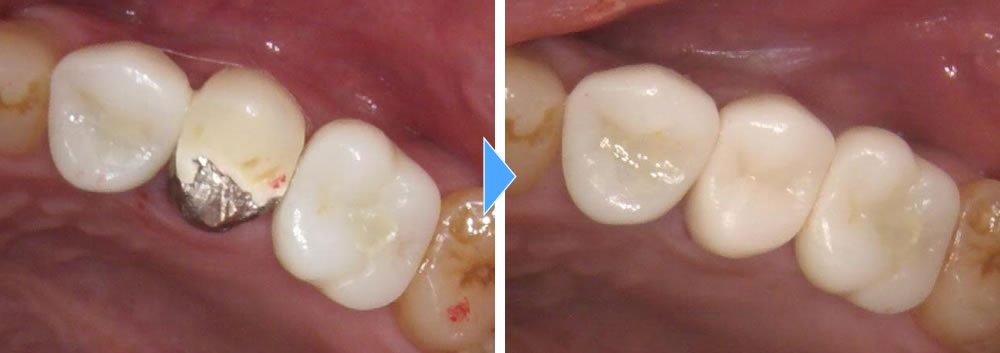

インプラント治療完了後の口腔内写真

その後、3ヵ月待ちしっかりと骨と結合しているのを確認後、上部のジルコニアの歯を作成しました。最終的に残りの真ん中の歯も綺麗にしたいとの事で、セラミッククラウンにて治療を行いました。